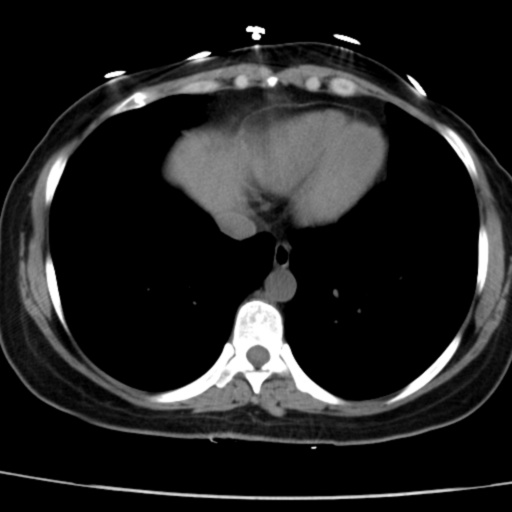

CT52091:女、42岁,B超提示肝右叶2X1cm肿块,请会诊。

上腹部CT轴位平扫未见明确异常;建议:行多期CT增强扫描检查。

上腹部CT平扫未见明确异常